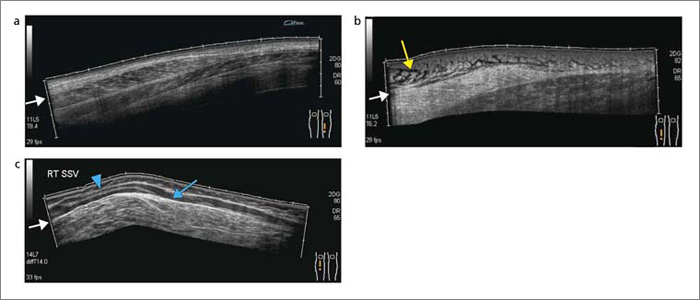

血管エコーパーフェクトガイド―動脈硬化の早期発見 (循環器臨床

血管エコーパーフェクトガイド―動脈硬化の早期発見 (循環器臨床

血管エコーパーフェクトガイド―動脈硬化の早期発見 (循環器臨床,

超音波検査(エコー検査) | あさひまちクリニック|旭川市旭町, エキスパートの手元がみえる!血管エコー〜解剖・正常像で身に,